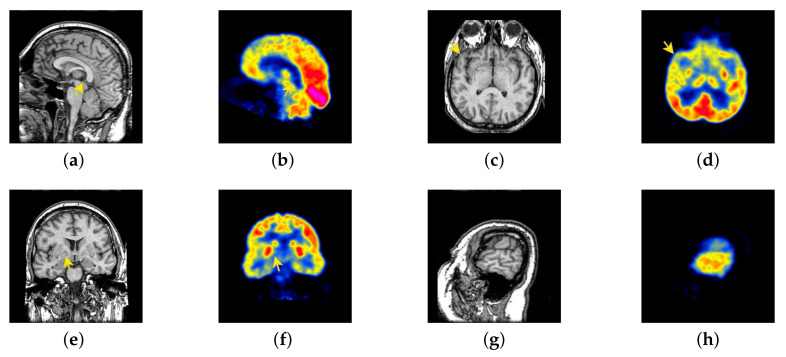

In this section, all FDG images are derived from the normal human brain, but the angle is chosen differently in Figure 24. In Figure 25, Figure 26, Figure 27 and Figure 28, we find that the color information obtained by the image fusion method based on NSCT, DTCWT, and LPSR is better preserved, but the structure information is lost more. The fusion image based on GFF, IGM, and FusionCNN method retains the complete structure information in the MRI image, but the color obtained from the FDG image is distorted. The image color information obtained by DDcGAN fusion method is too bright, resulting in unclear color area details and low contrast of color region. In contrast, the image obtained by our algorithm has moderate brightness of color information, complete structure information, and complete biological detail information.

Figure 24.

Four pairs of MRI-Fludeoxyglucose (FDG) source images: (a,c,e,g) are MRI images; (b,d,f,h) are FDG images.

The averaged subjective scores of MRI-FDG fused images obtained by 8 algorithms are shown in Figure 29 and Figure 30, and objective evaluation indicators are all shown from Figure 31, Figure 32, Figure 33, Figure 34, Figure 35, Figure 36, Figure 37, Figure 38, Figure 39 and Figure 40. Overall, our algorithm performs well in EN, FMI, RMSE, AG, SSIM, , , and . Our algorithm is the best of eight algorithms in the fusion of image structure information. In the metric of cross entropy and visual information fidelity, our algorithm is slightly inferior to other algorithms. However, from the overall evaluation, the algorithm has obvious advantages in fusion MRI and FDG.